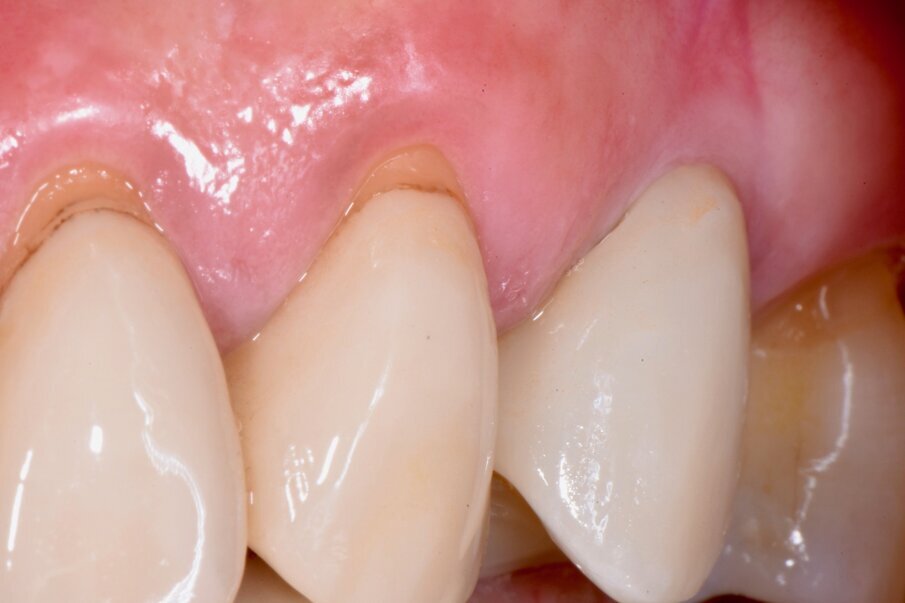

Tre mesi dopo, l’inserimento dell’impianto i volumi anatomici dei tessuti perimplantari presentano la stessa forma e dimensione di quella precedente dell’estrazione del dente (Fig. 3). Dopo il rilevamento dell’impronta digitale si disegnano i margini gengivali del manufatto protesico, prestando attenzione al profilo d’emergenza (Figg. 4a, 4b). La corona in disilicato di litio viene cementata rispettando i profili anatomici conservati dalla cappetta castomizzata (Fig. 5). A distanza di due anni si possono notare il mantenimento volumetrico delle strutture tessutali attorno al restauro implant-protesico.

Fig. 3 - Si può notare il trofismo e il volume dei tessuti periimplantari 3 mesi dopo l’inserimento dell’impianto.

Fig. 5 - I volumi dei tessuti perimplantari sono sovrapponibili a quelli registrati prima dell’estrazione dentale.

Fig. 6a - Caso clinico a due anni dalla finalizzazione implanto-protesica.